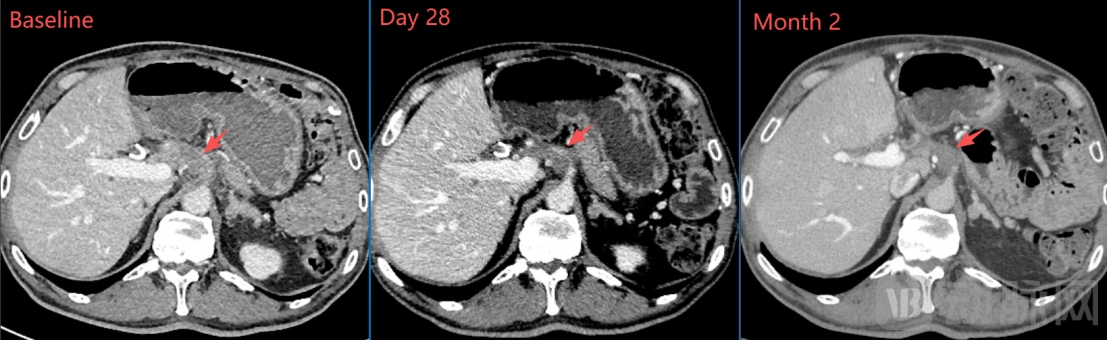

一个月的影像学检查显示:肝门区靶病灶明显缩小、肺部靶病灶基本完全消失,靶病灶直径之和从基线期的67mm缩小至43mm(下降35.8%),按RECIST1.1标准评估已达到部分缓解(PR);两个月的影像学检查显示:肿瘤病灶维持PR,且靶病灶直径之和进一步缩小至35mm(下降47.8%)。